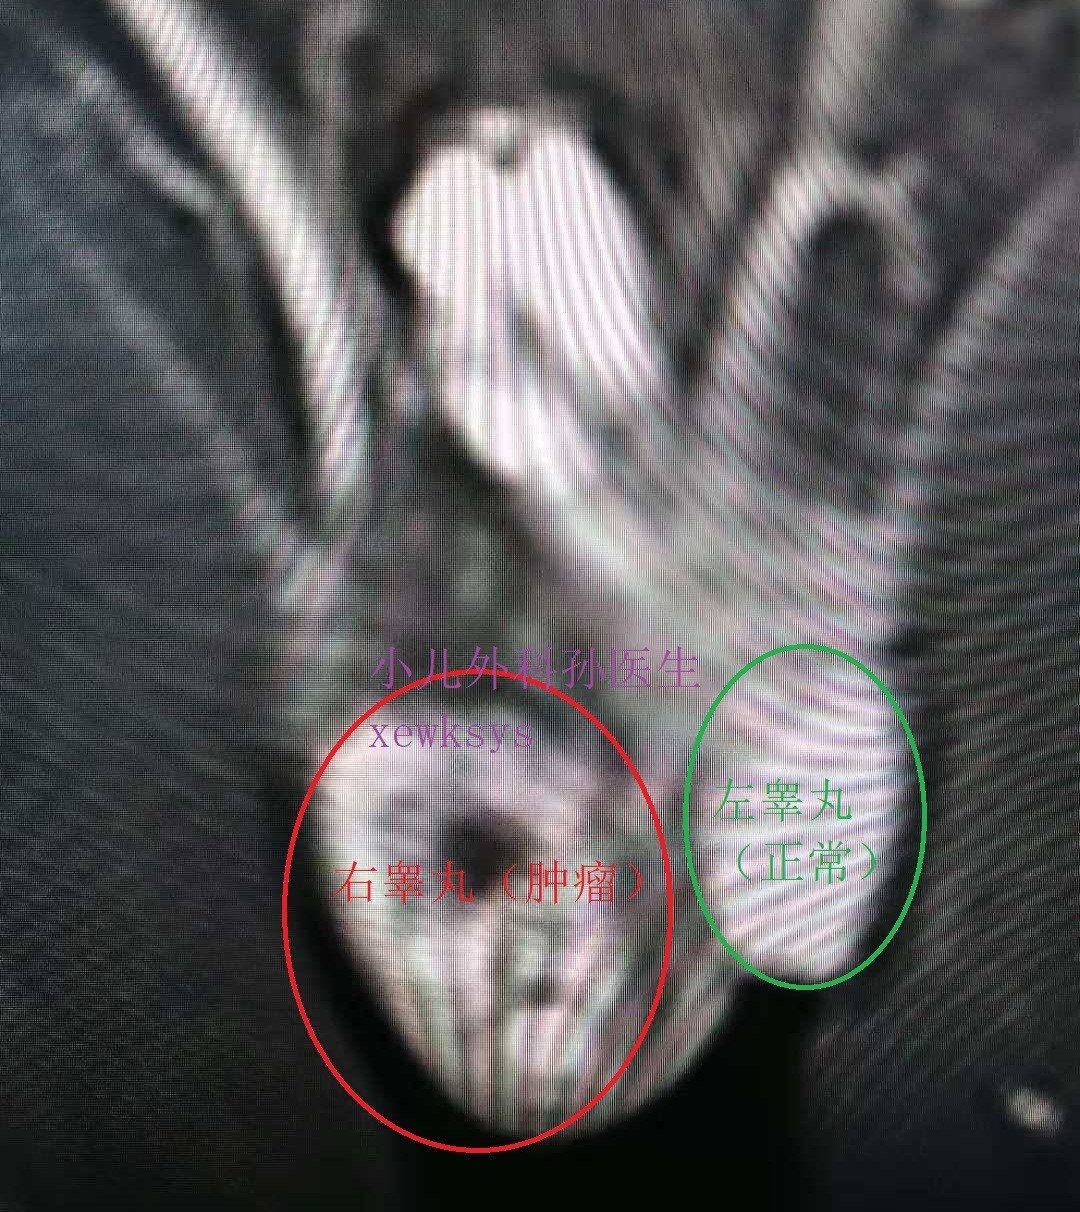

发现睾丸肿瘤以后,医生还可能会给孩子做个磁共振(MR)。

上图:MR右睾丸明显增大,全部为肿瘤占据